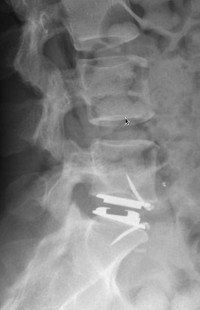

Spondylolisthesis lombaire

Discopathies